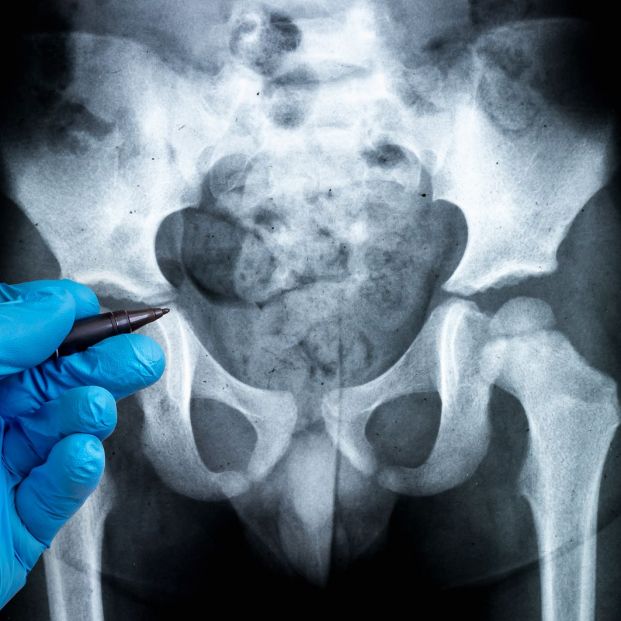

Sin embargo, el raquitismo también puede afectar a la población adulta y eso lo que se conoce como osteomalacia. Una enfermedad del metabolismo óseo que se traduce en un déficit de mineralización del hueso que viene acompañado de dolores o fracturas y especialmente llamativo en el caso de las personas mayores entre los que suele ser muy común como recuerdan desde la Sociedad Española de Medicina Interna (@Sociedad_SEMI).

Las primeras señales que acompañan a un diagnóstico previo de esta patología se refieren a dolor en los huesos (sobre todo en la parte baja de la espalda, pelvis o las piernas) que se pueden incrementar durante la noche. A esto debemos sumar la debilidad muscular que sienten estos pacientes, espasmos y temblores musculares, así como una mayor sensibilidad cuando se presionan estos huesos.